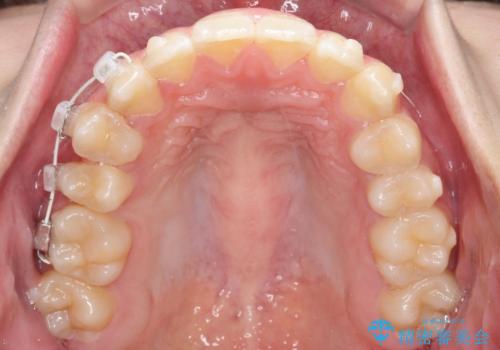

- インビザライン

- 右上の小臼歯が大きくねじれており、噛み合わせや見た目に影響を与えている状態でした。診察の結果、インビザライン単独では十分な回転が得られにくいと判断。そのため、基本的な歯列の移動はインビザラインで行いながら、部分的にワイヤー矯正を併用するコンビネーション治療を計画しました。

まず、インビザラインで歯列全体を整えながら、スペースを確保しました。その後、部分ワイヤーを装着し、右上小臼歯の捻転を効率よく改善。ワイヤーの力を活用することで、より確実に歯の向きを整えることができました。治療後は、「しっかり噛めるようになり、見た目も自然になった」と患者様にもご満足いただきました。